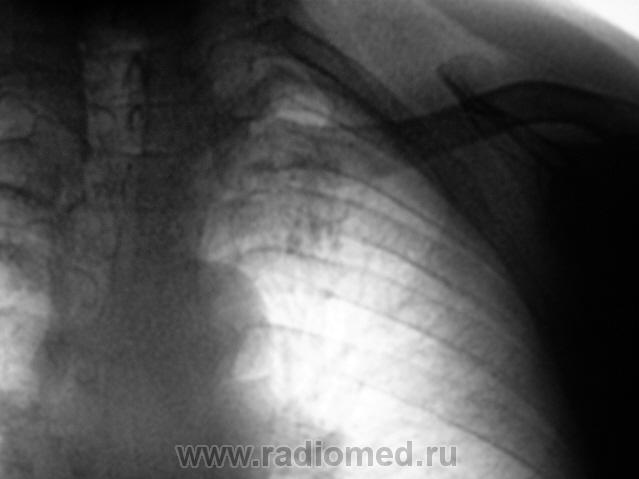

Пол пациента: Мужской пол Тип патологии: Инфекция Область исследования: Грудная клетка и верхние дыхательные пути Методы исследования: Rg При расшифровке флюорограмм пациент взят "на контроль". Известно, что на учете пациент не состоял, со слов пациента "ничем не болел". Произведено стандартное исследование - рентгенография и томография в стандартных срезах. Ваше мнение коллеги? Пнд, 23/11/2009 - 19:34 #1 Глазков Игорь А... Не на сайте Был на сайте: 1 год 2 месяцев назад Зарегистрирован: 19.12.2008 - 20:41 Публикации: 1597 инфильтративного туберкулёза слева в верхней доле Прийди к Себе

инфильтративного туберкулёза слева в верхней доле